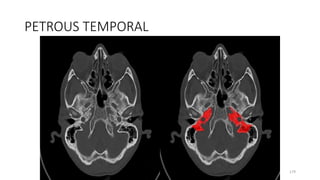

PETROUS TEMPORAL

Content